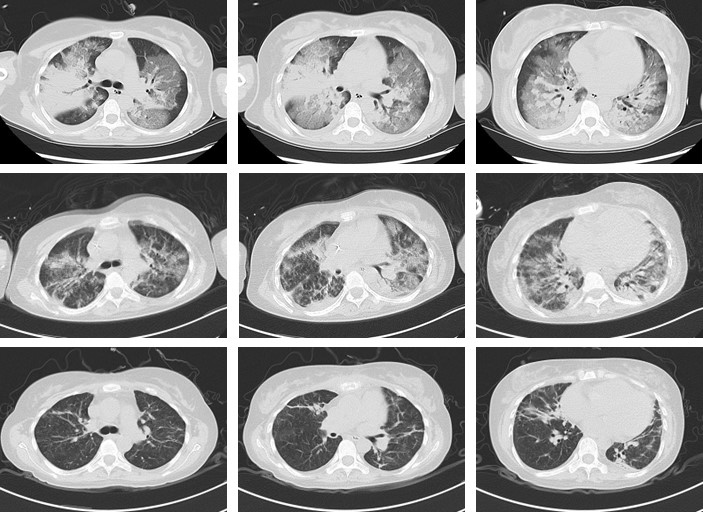

肺部感染炎症及肺水肿等影像学改变显示患者恢复良好

ECMO支持治疗第8天,患者病情趋于稳定,意识转清,氧合好转,经重症医学科吴大玮教授、王昊教授、李琛教授、郭海鹏教授评估后成功撤离ECMO。在护士长张蔚团队的精心照护下,患者逐渐脱离呼吸机,拔除气管插管,续贯经鼻高流量湿化氧疗。患者CT及超声检查提示,肺部感染炎症明显吸收、子宫及下肢血管恢复良好。经过40余天精心救治,患者顺利康复出院。